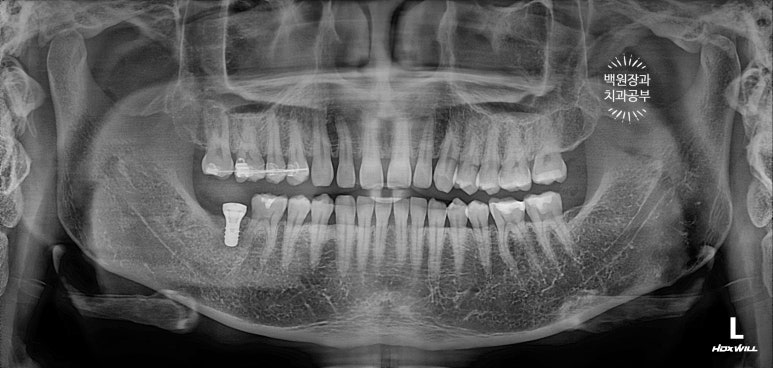

가장 먼저 문제가 되었던 오른쪽 아래 두번째 큰 어금니를 발치했습니다.

아울러 위치가 좋지 않았던 위아래 사랑니도 발치했어요.

보시면, 치아 세개가 없어진것을 보실 수 있을거에요.!!

사실 이뽑고 3달이 지난 시점의 치과용 파노라마 사진이라, 이미 이 뽑은 흔적조차 남아있지 않네요...

보시면 오른쪽 위 치아 4개에 교정장치가 붙어있는 것을 보실 수 있을거에요.

일반적으로 큰어금니를 밀어넣는 (함입) 교정치료는 그 정출량에 따라 다르지만, 약 6-9개월 정도의 치료기간을 요합니다. 본 환자분 같은 경우에는 정출된 양이 적었기 때문에 전체 치료기간이 약 5개월 정도였어요!